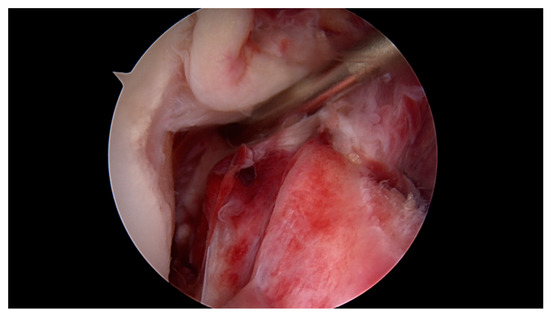

Primary Proximal ACL Repair: A Biomechanical Evaluation of Different Arthroscopic Suture Configurations

by Steffen B. Rosslenbroich, Andrea Achtnich, Cathrin Brodkorb, Clemens Kösters, Carolin Kreis, Sebastian Metzlaff, Benedikt Schliemann and Wolf Petersen

J. Clin. Med. 2023, 12(6), 2340; https://doi.org/10.3390/jcm12062340 - 17 Mar 2023

Purpose: Several suture techniques have been described in the past for direct ACL repair with poor healing capacity and a high re-rupture rate. Therefore, we investigated a refixation technique for acute primary proximal ACL repair. The purpose of this study is to [...] Read more.

Purpose: Several suture techniques have been described in the past for direct ACL repair with poor healing capacity and a high re-rupture rate. Therefore, we investigated a refixation technique for acute primary proximal ACL repair. The purpose of this study is to compare the biomechanical properties of different suture configurations using a knotless anchor. Methods: In this study, 35 fresh-frozen porcine knees underwent proximal ACL refixation. First, in 10 porcine femora, the biomechanical properties of the knotless anchor, without the ligament attached, were tested. Then, three different suture configurations were evaluated to reattach the remaining ACL. Using a material testing machine, the structural properties were evaluated for cyclic loading followed by loading to failure. Results: The ultimate failure load of the knotless anchor was 198, 76 N ± 23, 4 N significantly higher than all of the tested ACL suture configurations. Comparing the different configurations, the modified Kessler–Bunnell suture showed significant superior ultimate failure load, with 81, 2 N ± 15, 6 N compared to the twofold and single sutures (50, 5 N ± 14 N and 37, 5 ± 3, 8 N). In cyclic loading, there was no significant difference noted for the different configurations in terms of stiffness and elongation. Conclusions: The results of this in vitro study show that when performing ACL suture using a knotless anchor, a modified Kessler–Bunnell suture provides superior biomechanical properties than a single and a twofold suture. Within this construct, no failure at the bone–anchor interface was seen. Clinical relevance: Since primary suture repair techniques of ACL tears have been abandoned because of inconsistent results, ACL reconstruction remains the gold standard of treating ACL tears. However, with the latest improvements in surgical techniques, instrumentation, hardware and imaging, primary ACL suture repair might be a treatment option for a select group of patients. By establishing an arthroscopic technique in which proximal ACL avulsion can be reattached, the original ACL can be preserved by using a knotless anchor and a threefold suture configuration. Nevertheless, this technique provides an inferior ultimate failure load compared to graft techniques, so a careful rehabilitation program must be followed if using this technique in vivo. Full article

Show Figures

Figure 1